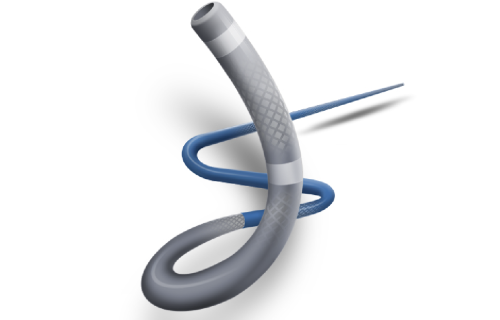

Na área de Cardiologia Intervencionista, fornecemos dispositivos de ponta, como stents, cateteres e balões, que são essenciais para a realização de angioplastias e outros procedimentos cardíacos minimamente invasivos. Nossos produtos são projetados para oferecer máxima eficiência e segurança, contribuindo para a rápida recuperação dos pacientes e a redução de complicações pós-operatórias.

Além disso, fornecemos soluções para o tratamento de feridas que promovem a cicatrização eficiente e segura para os pacientes. Nossos dispositivos de Terapia por Pressão Negativa são projetados para criar um ambiente ideal de cura, reduzindo o risco de infecções e acelerando o processo de cicatrização. Essas soluções são amplamente utilizadas em feridas crônicas,

úlceras de pressão, feridas pós-cirúrgicas e traumas, oferecendo uma alternativa eficaz e inovadora para o manejo de feridas complexas.